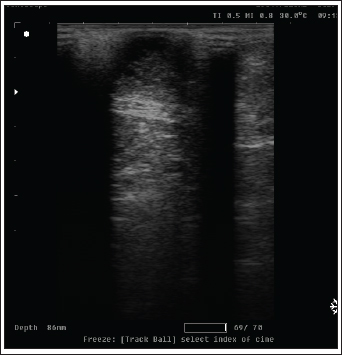

Fig. 3. Radiography images of mammary gland tissue showing enlargement of the mammary glands with intact body wall in different affected female cats. UltrasonographyOn ultrasound images, mammary gland tissue showed higher echogenicity than normal tissue. The FMH lesions were well-defined, slightly hyperechoic, lobulated masses containing multiple small anechoic clefts within the mammary parenchyma. The intraductal pattern is dominant, with anechoic areas corresponding to clefts of different shapes within the mammary gland parenchyma. The presence of clefts in mammary fibroepithelial lesions provided a more heterogeneous appearance to the ultrasound images (Fig. 4). In the solid lesions, the ultrasound pattern is more homogeneous (Fig. 5).

Fig. 4. Ultrasonographic image of lesions presenting cleft-like anechoic areas and characteristics of the intraductal pattern.